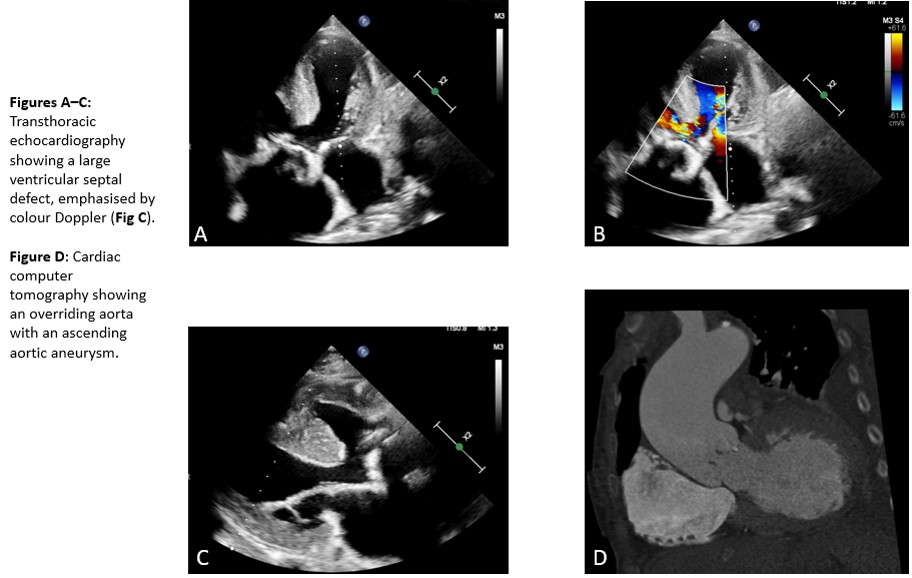

Echocardiography and cardiac CT revealed an unrepaired TOF with a subvalvular ventricular septal defect (2.4 cm), pulmonary stenosis or right ventricular outflow obstruction respectively, overriding aorta, and right ventricular hypertrophy. Additional findings included an aneurysm of the ascending aorta (5.7 cm), severe aortic stenosis with moderate regurgitation, and severe tricuspid regurgitation with bilateral pleural effusions. Coronary angiography excluded coronary artery disease. Laboratory testing showed elevated troponin (300,000 ng/L) and lactate (4 mmol/L). Staphylococcus saprophyticus was isolated from blood cultures, sensitive to initiated antibiotic therapy.